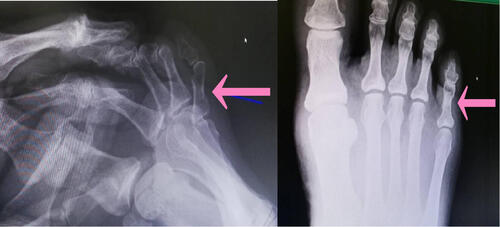

結果「右足第5基節骨骨折」と判明。

骨折線の入り方、部位を明確にし、骨癒合促進の為、

マイオパルスにて加療を行っていきます。

とくに足指で多いのは、今回と同じ基節骨といわれる指の付け根の骨。

骨折と同時に脱臼したり、粉々に骨折しない限り、手術になることはないですが、

しっかり骨折線を確認しながら治療を施していかないと、

オーバーラップと言って、隣の指と重なったり、

手を握ったときに、違う方向に向いてしまったりします。

なので、レントゲン、エコー画像を確認しながら、適切な治療、固定が必要です。